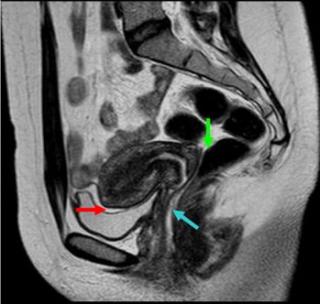

Магнитно-резонансная томография при эндометриозе позволяет точно определить степень продвижения и площадь поражения.

Что видно в результатах

Результаты МРТ показывают:

- утолщение стенок матки;

- эндометрий в яичниках, маточных трубах;

- небольшие кисты в соединительной или мышечной ткани;

- неоднородность структуры тканей;

- спайки и узелки.